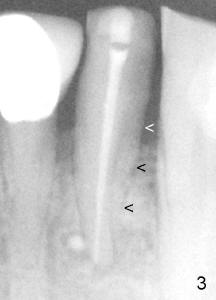

Sixty-two year old Chinese man presented to my office for new patient exam in June 2009. He has history of bruxism and wears night guard (Fig.1). The tooth #25 has incisal composite (*) with mild percussion. PAs show + PARL associated with #25 (Fig.2) and possible missing one canal (Fig.3; arrowheads point to possible 2nd root). RCT retreat was suggested. Extraction and implant were proposed as an alternative. In the next two 6-month appointments, he complained of mild pain in lower front tooth sometimes. RCT retreat was initiated on June 16, 2010. After removing composite, GP was removed with Chloroform and hand files. WL was determined by Root XZ at 15 mm. Debridement was done with hand files until #20 and rotary files until 30/.06 (Fig.4). The second canal was not found. It appears that some of GP was pushed outside of apical constriction (Fig.5 after Cavit). Twelve days later the patient returned to finish RCT retreat. It appears that symptoms improved after initiation of RCT retreat, although percussion is still mild. After removing Cavit and redebridement with #30 hand file, #10 precurved K file was inserted several times at different directions, hopefully getting into 2nd canal, which was not found. RCT filling was finished using AH Plus paste, master cone, lateral condensation with 1 medium fine accessory GP and vertical condensation (Fig.6). Composite build up was done immediately. Six months later, the patient insisted that pain is reduced substantially, but there is still mild percussion. PA shows persistent PARL (Fig.7 with outline with 2nd root (arrowheads)). Twelve months after RCT retreat, the patient is symptom-free, but objectively is not (including mild percussion and slightly enlarging PARL (Fig.8)). The 2nd canal is apparently lightly filled (red arrowhead).